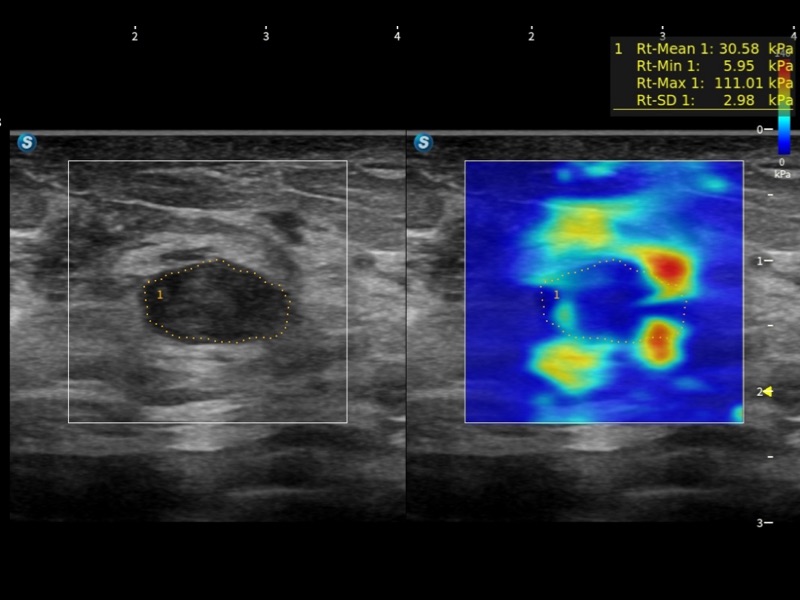

S-MSK肌骨自动标注 URI-CEUS超分辨造影成像技术 S-Fetus®凤眼 SWE剪切波弹性成像 ATI组织声衰减成像 Contrast HFR高帧率造影 SonoFusion融合成像 S-Thyroid甲状腺自动测量 S-Breast 乳腺自动测量